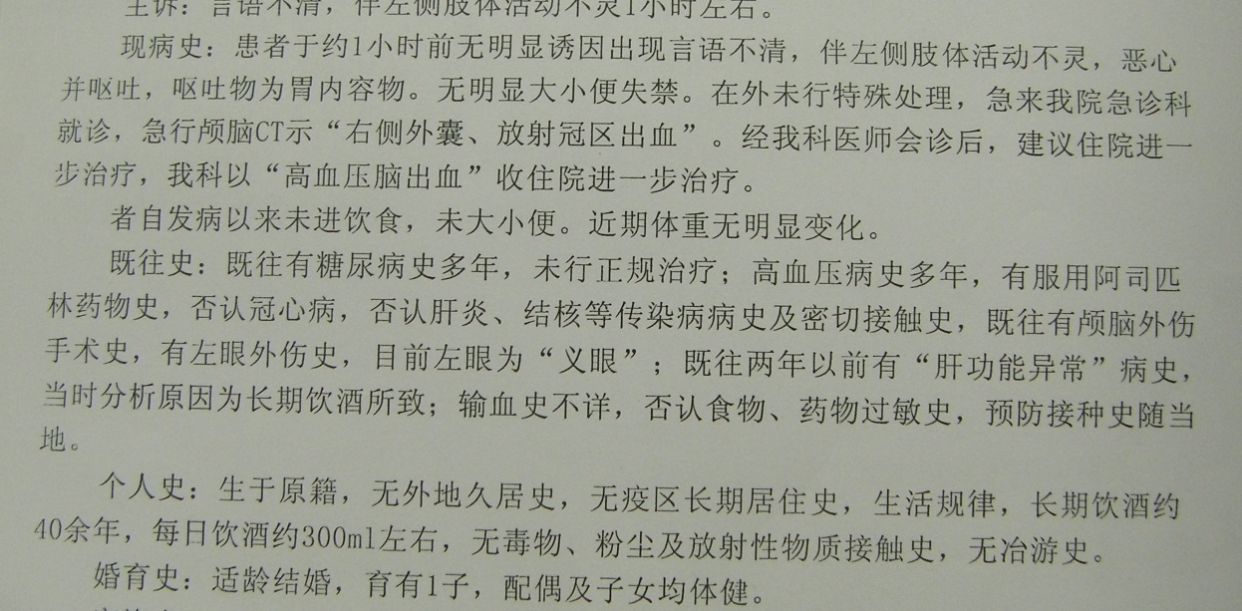

例1,男,61岁,言语不清伴左侧肢体活动障碍1小时入院。

CT示右基底节区脑出血,占位明显,中线移位。因出现右侧瞳孔增大,急症全麻下开颅血肿清除去骨瓣减压。

术后1天CT复查,血肿清除满意,中线恢复。

术后半月CT复查示,水肿基本消退,脑室无扩大。